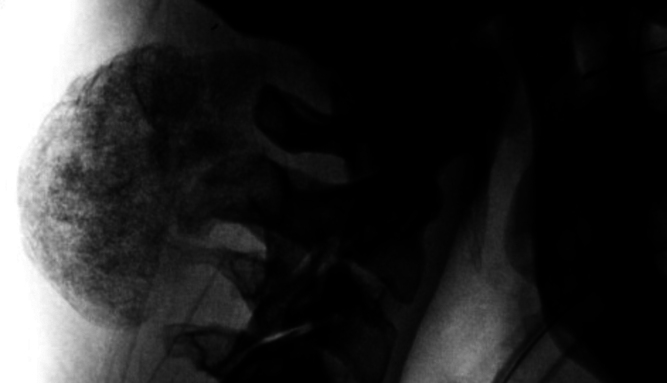

背景:骨外骨软骨瘤是一种界限明确的骨软骨性病变,起源于没有骨连续性的软组织。骨外骨软骨瘤可能出现在关节旁位置,尽管很少有报道的病例发生在脊柱附近。临床诊断仍然具有挑战性,因为这些肿瘤很难与其他骨化软组织病变区分开来。治疗包括观察或切除。在这里,作者提出一个罕见的病例骨外骨软骨瘤附近的颈椎。观察:56岁男性,表现为可触及的左侧椎骨旁枕骨下肿块,缓慢进展超过5年。患者无症状,神经学检查无局灶性。MRI显示左侧枕下区约6厘米边界清晰的非均匀肿块,与脊柱或颅骨没有直接接触。在t2加权MRI上发现一个低信号囊,在T1和t2加权MRI上发现多个低信号分隔。肿瘤生长缓慢提示为良性肿瘤。胸部、腹部和骨盆的CT检查排除了恶性肿瘤。手术干预被提出并被患者接受。术后2个月,影像学显示无复发,患者无症状,活动范围改善。结论:在诊断骨软骨旁肿块时应考虑骨骼外骨软骨瘤。https://thejns.org/doi/10.3171/CASE25468。

Observations: A 56-year-old male presented with a palpable left paraspinal suboccipital mass that had slowly progressed over 5 years. The patient was asymptomatic and the neurological examination was nonfocal. MRI revealed an approximately 6-cm well-circumscribed heterogeneous mass in the left suboccipital area that lacked direct contact with the spine or calvarium. A hypointense capsule on T2-weighted MRI and multiple hypointense septations on T1- and T2-weighted MRI were identified. The slow rate of tumor growth suggested a benign tumor. CT imaging of the chest, abdomen, and pelvis was obtained to rule out malignancy. Surgical intervention was offered and accepted by the patient. At 2 months postoperatively, imaging demonstrated no recurrence, and the patient was asymptomatic and had improved range of motion.